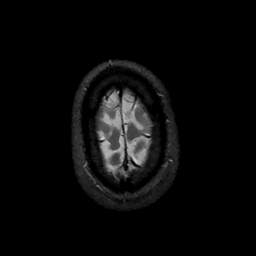

MR Study #11, May 5, 1991 -- Slice #46